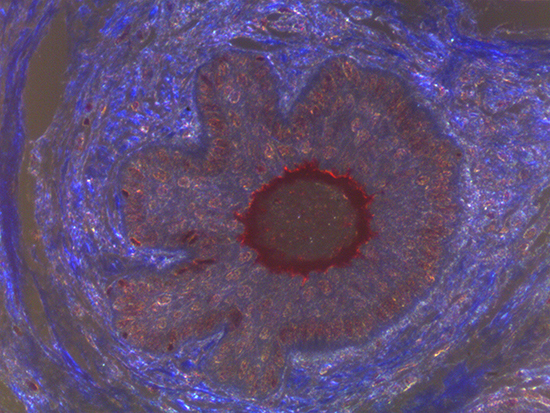

Figure 2: Darkfield Imaging of Dermal Tissue

When comparing Figures 1 and 2, the visual differences are significant. A brightfield image is formed with the illumination source below the sample, and then transmitted light propagates through the sample to the sensor forming a bright, white background with sharp color. A darkfield image is formed by directing light at an oblique angle through the sample, forming a hollow cone of light which is collected by the objective. Darkfield illumination typically yields a dark background with sharp color, but in the case of Figure 2, the collagen and muscle fibers interfered with the light path and caused a blur of light and color. The dark background is hardly evident and only two distinct colors are visible. When analyzing histological stains, brightfield illumination is the preferred technique for lighting a sample.